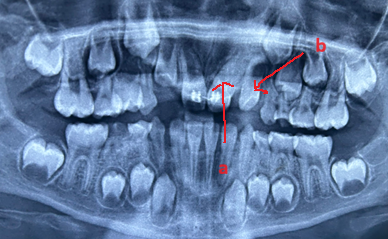

image 20231218155055 1

Mesiodents               Paramolar Distomolar(a), Paramolar (b)

Hình 1: Các loại răng thừa